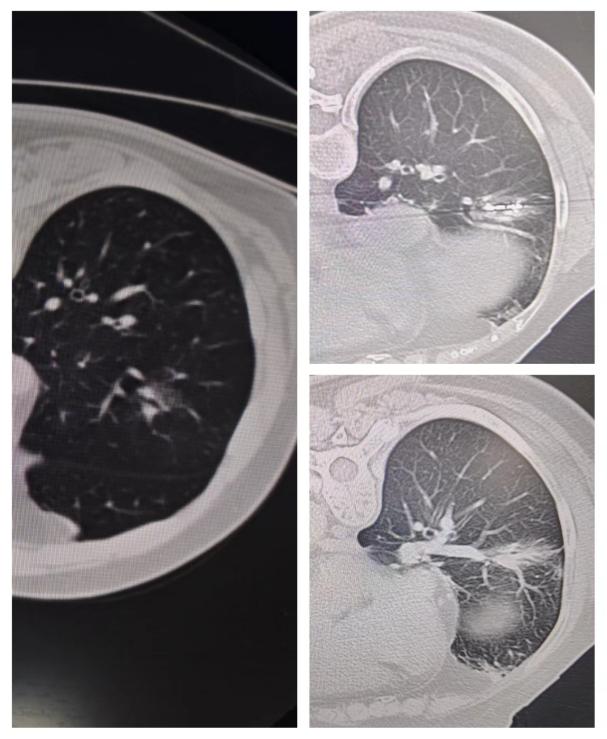

患者李某,71岁,1年前体检胸部CT提示右肺下叶磨玻璃结节,大小约1.6X.5mm;今年6月复查磨玻璃结节呈增大趋势,并发现变性成分,影像考虑高危结节。因患者年龄较大,家属得知我院可以行肺结节的微创治疗,能最大程度减少患者肺部损伤达到根治效果,遂慕名入住我院决定行肺部结节微波消融术。CT科阚庆玲主任与闫强主治医师详细询问患者病史,积极完善相关检查后发现患者肺内结节呈磨玻璃实性结合,属高危结节。阚庆玲主任医师团队缜密研判并经患者及家属同意后决定为其施耐受性较好的CT引导下经皮肺结节微波消融术。